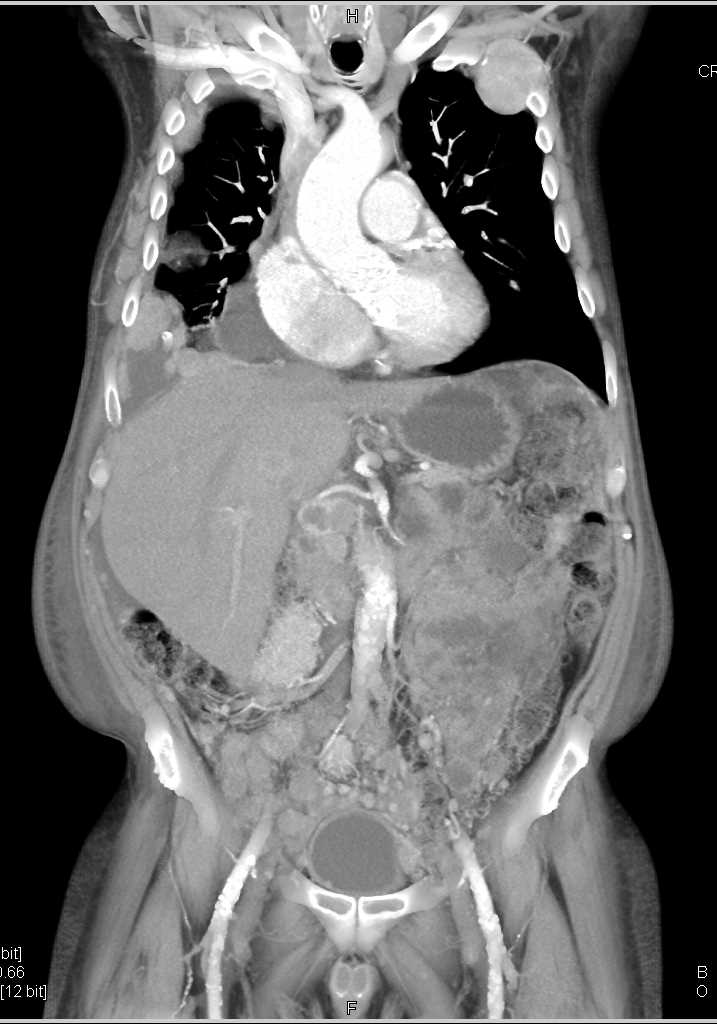

Carcinomatosis with Widespread Metastatic Colon Cancer